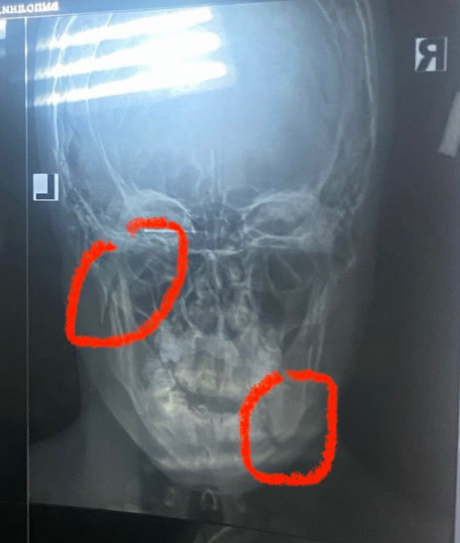

Получаю закрытый двусторонний перелом нижней челюсти. Еду в местную травму(живу в пригороде). Там мне сообщают что тут таких врачей нет, надо в Питер. Но делают этот чудный снимок.

Приходит понедельник, утро, ОН -- мой спаситель, мой лечащий врач. Ну что же скажете вы мне? А он скажет что я мне нужна вторая операция. Остеосинтез, если я не ошибаюсь. Нужны 2 пластины (как перфолента) и 9 винтов к ней (тупые клопы бля)

Только вот материалы нужны импортные, немецкие, цена вопроса 89000 за комплект пластины и винтов умножить на 2, т.к. нужны таких 2.